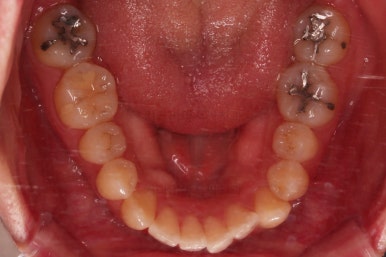

초진 시, 입안의 모습입니다.

좌측 송곳니가 덧니처럼 튀어나가 있고, 송곳니 옆의 작은 억므니가 안으로 쏙 들어가서 덧니 느낌이 더 강조되어 보이네요.

위아래 앞니가 긴밀하게 겹침이 없는 약간의 개방교합(오픈바이트, Openbite) 경향이 보입니다.

개방교합을 개선하면서 교합을 맞춰주고요.

디테일한 중앙선이라던지, 안에서 끄집어낸 치아의 각도라던지 비롯해서 환자분이 원하시는 느낌을 반영해서 마무리를 합니다.

1년 2개월이라는 비교적 짧은 기간안에 원하시는 부분을 깔끔하게 개선했습니다.